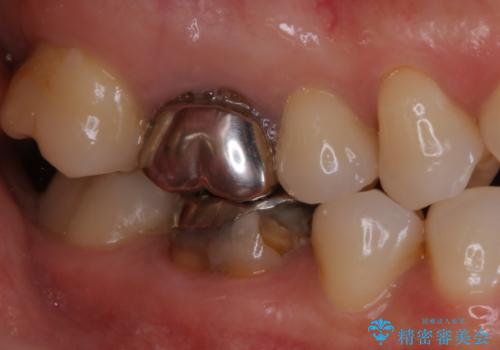

- 歯が欠けてしまったと来院された方です。

メタルインレーが一部欠けており、その下には大きな虫歯ができていました。

再精密根管治療もご提案しましたがご希望されなかったため、今回は土台と被せ物のみ治療介入しました。